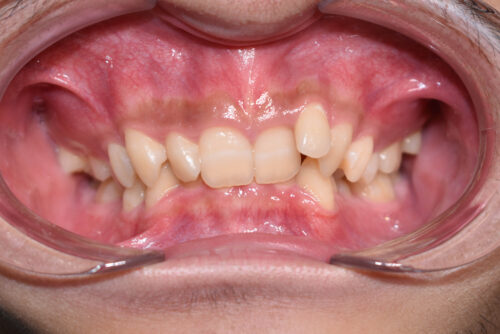

初診時年齢 17歳 男性

歯のでこぼこ (叢生)と

咬み合わせの深さ (過蓋咬合)を

気になさって

豊島区 巣鴨駅より ひとつ となり駅の

矯正歯科専門クリニック 大塚たまみ矯正歯科

へ いらっしゃいました。

歯のがたつき(叢生)が強く認められ

また下の歯が 全く見えず 過蓋咬合の状態でした。